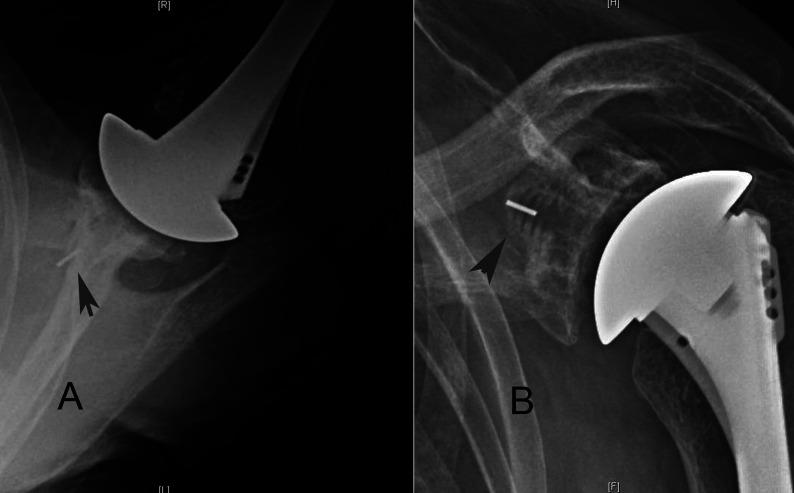

This study evaluated the ability of shoulder arthroplasty using a standard glenoid component to improve patient self-assessed comfort and function and to correct preoperative humeral-head decentering on the face of the glenoid in patients with primary glenohumeral arthritis and type-B2 or B3 glenoids.

We identified 66 shoulders with type-B2 glenoids (n = 40) or type-B3 glenoids (n = 26) undergoing total shoulder arthroplasties with a non-augmented glenoid component inserted without attempting to normalize glenoid version and with clinical and radiographic follow-up that was a minimum of 2 years. The Simple Shoulder Test (SST), the percentage of humeral-head decentering on the glenoid face, and bone ingrowth into the central peg were the main outcome variables of interest. Similar analyses were made for concurrent patients with type-A1, A2, B1, and D glenoid pathoanatomy to determine if the outcomes for type-B2 and B3 glenoids were inferior to those for the other types.

The SST score (and standard deviation) improved from 3.2 ± 2.1 points preoperatively to 9.9 ± 2.4 points postoperatively (p < 0.001) at a mean time of 2.8 ± 1.2 years for type-B2 glenoids and from 3.0 ± 2.5 points preoperatively to 9.4 ± 2.1 points postoperatively (p < 0.001) at a mean time of 2.9 ± 1.5 years for type-B3 glenoids; these results were not inferior to those for shoulders with other glenoid types. Postoperative glenoid version was not significantly different (p > 0.05) from preoperative glenoid version. The mean humeral-head decentering on the glenoid face was reduced for type-B2 glenoids from -14% ± 7% preoperatively to -1% ± 2% postoperatively (p < 0.001) and for type-B3 glenoids from -4% ± 6% preoperatively to -1% ± 3% postoperatively (p = 0.027). The rates of bone integration into the central peg for type-B2 glenoids (83%) and type-B3 glenoids (81%) were not inferior to those for other glenoid types.

Shoulder arthroplasty with a standard glenoid inserted without changing version can significantly improve patient comfort and function and consistently center the humeral head on the glenoid face in shoulders with type-B2 and B3 glenoids, achieving >80% osseous integration into the central peg. These clinical and radiographic outcomes for type-B2 and B3 glenoids were not inferior to those outcomes for other glenoid types.

本研究评估了在原发性盂肱关节炎且为B2型或B3型肩胛盂的患者中,使用标准肩胛盂假体进行肩关节置换术改善患者自我评估的舒适度和功能,以及纠正术前肱骨头在肩胛盂表面偏心的能力。

我们确定了66例接受全肩关节置换术的肩胛盂,其中40例为B2型肩胛盂,26例为B3型肩胛盂,植入非增强型肩胛盂假体时未试图使肩胛盂角度正常化,临床和影像学随访至少2年。简易肩关节测试(SST)、肱骨头在肩胛盂表面的偏心百分比以及骨长入中心栓是主要关注的结局变量。对同时患有A1型、A2型、B1型和D型肩胛盂病理解剖的患者进行了类似分析,以确定B2型和B3型肩胛盂的结局是否劣于其他类型。

对于B2型肩胛盂,在平均2.8±1.2年时,SST评分(及标准差)从术前的3.2±2.1分提高到术后的9.9±2.4分(p<0.001);对于B3型肩胛盂,在平均2.9±1.5年时,SST评分从术前的3.0±2.5分提高到术后的9.4±2.1分(p<0.001);这些结果并不劣于其他肩胛盂类型的肩关节。术后肩胛盂角度与术前相比无显著差异(p>0.05)。B2型肩胛盂肱骨头在肩胛盂表面的平均偏心度从术前的-14%±7%降至术后的-1%±2%(p<0.001),B3型肩胛盂从术前的-4%±6%降至术后的-1%±3%(p=0.027)。B2型肩胛盂(83%)和B3型肩胛盂(81%)骨长入中心栓的比例不低于其他肩胛盂类型。

植入标准肩胛盂且不改变角度的肩关节置换术可显著改善患者舒适度和功能,并持续使B2型和B3型肩胛盂肩关节的肱骨头在肩胛盂表面居中,实现中心栓骨整合率>80%。B2型和B3型肩胛盂的这些临床和影像学结局并不劣于其他肩胛盂类型。